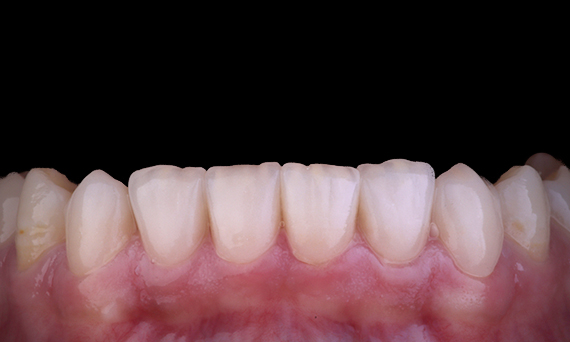

Beim Ersatz eines oberen zentralen Schneidezahns durch eine implantatgetragene festsitzende Prothese sind Fallauswahl, Planung und die sorgfältige Anwendung der Behandlungsmethoden der Schlüssel zum Erfolg. Eine sofortige Implantat-Platzierung und eine Restauration können den Gewebeverlust minimieren und zu einem sehr ästhetischen Ergebnis führen. Die Implantat-Platzierung mit einem vollständig geführten Ansatz kann die Genauigkeit der Platzierung verbessern, und das Einsetzen des definitiven Abutments oder der Restauration zum Zeitpunkt der Implantat-Platzierung kann die Gewebestabilität fördern.

Dr. Alan Yap, Prosthodontist, Sydney, Australien